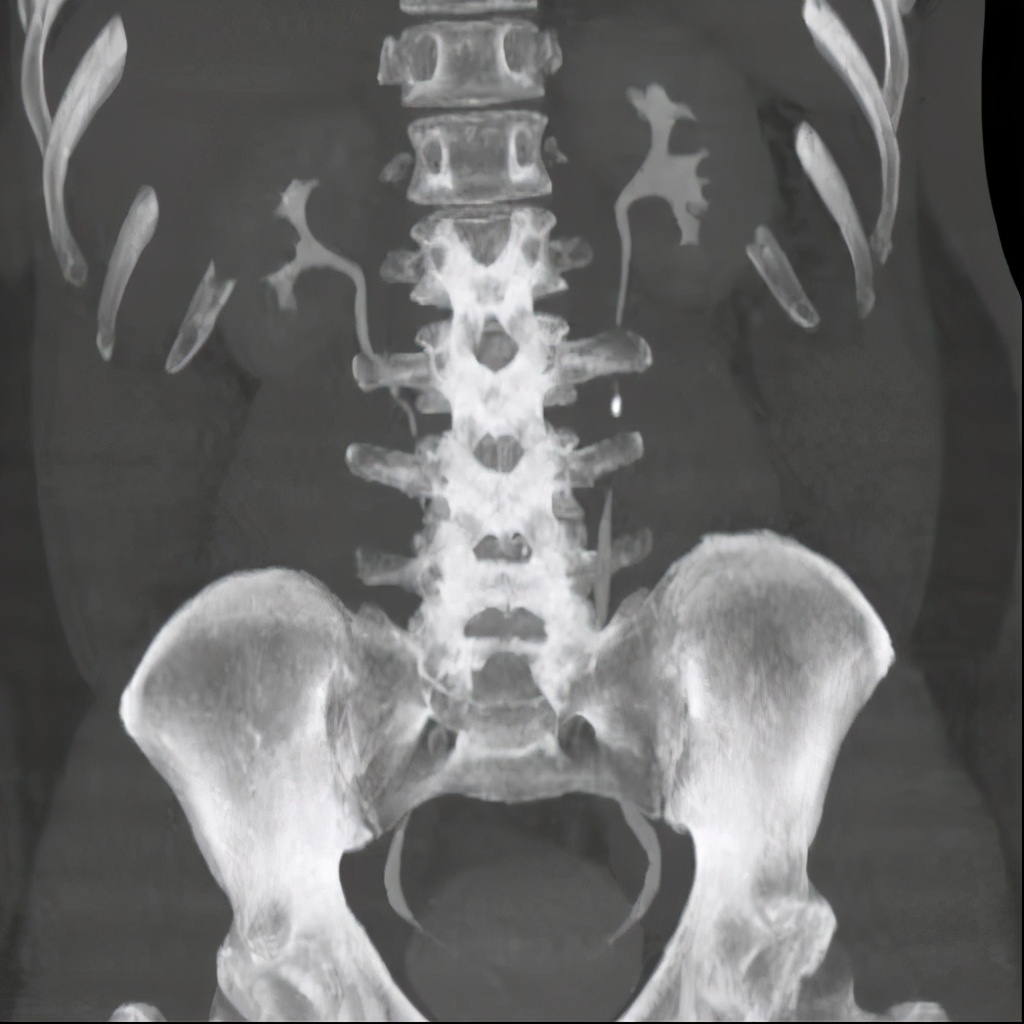

上图为泌尿系平扫后重建,可见左侧输尿管中段结石。

下图为静脉注射造影剂后,进行一定时间延迟后进行扫描、重建,见结石影与造影剂对比良好。